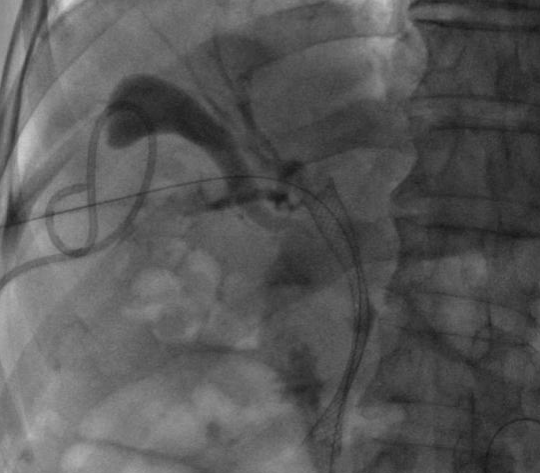

ERCP(內(nèi)鏡逆行胰膽管造影術(shù))是膽胰疾病精準(zhǔn)內(nèi)鏡診療技術(shù),具有不開腹、風(fēng)險(xiǎn)小、創(chuàng)傷小、恢復(fù)快、住院時(shí)間大大縮短的優(yōu)點(diǎn),尤其是對年齡大、體弱多病的患者尤為適宜。ERCP主要運(yùn)用于膽總管結(jié)石的取出,以及在經(jīng)口膽道子鏡的輔助下完成肝內(nèi)膽管結(jié)石的取出。

0b4174cdbf1f4e508687f388367c9ca6.Jpeg

bc72d6558d394d8ea787e762f054a7c5.Jpeg74bcac877ae44a9da8e58dab53d178ee.Jpeg75e90c629e6545de9ee764d5e15bc91e.JpegERCP取出膽總管結(jié)石

對于無法手術(shù)切除的膽管或胰腺惡性腫瘤導(dǎo)致的梗阻性黃疸,可以進(jìn)行ERCP下膽道支架植入,以緩解梗阻性黃疸癥狀,提高患者生活質(zhì)量。通過光動(dòng)力、射頻消融等治療,還可以控制腫瘤的生長,提高膽道支架的通暢期,延長患者生存時(shí)間。